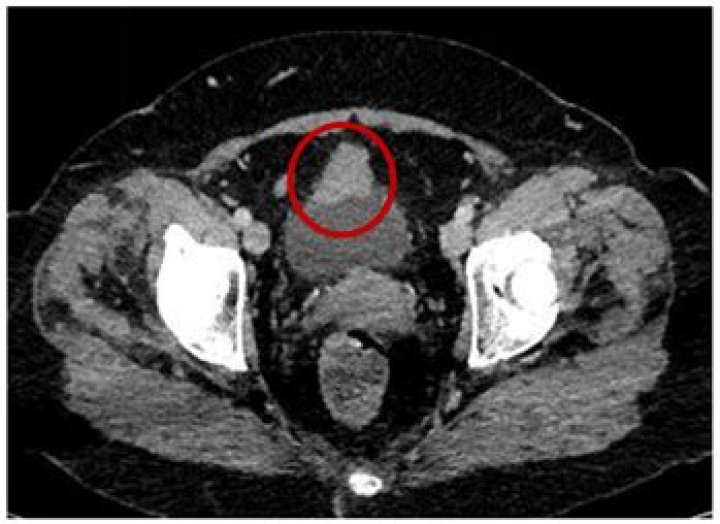

What is a urachal mass?

Urachal cyst develops when urachus remains patent in between the closed umbilical and vesical endpoints. It usually occurs in the lower third, close to the urinary bladder. It remains usually asymptomatic and diagnosed incidentally. As with other urachal remnants, most common complication is infection [3].

A urachal cyst develops if the urachus closes at both the umbilicus and the bladder but remains patent between these two endpoints. It occurs primarily in the lower one-third of the urachus and less frequently in the upper one-third (,19).